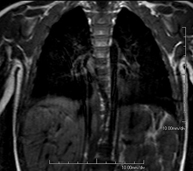

Prueba diagnóstica no invasiva que consiste en la obtención de imágenes de alta definición anatómica del mediastino mediante el empleo de un campo electromagnético y ondas de radio (con un emisor y un receptor). No utiliza radiación ionizante. El mediastino es la parte central de la caja torácica que incluye el timo, los grandes vasos (aorta torácica, vena cava inferior y superior, etc.), el corazón, la tráquea y los bronquios principales, ganglios linfáticos mediastínicos e hiliares, el esófago, etc. Está especialmente indicada en lesiones mediastínicas para diferenciar si son quísticas o sólidas, en el diagnóstico diferencial de las lesiones del mediastino anterior, etc. En ocasiones se deberá emplear contraste paramagnético (Gadolinio) para completar el estudio. - RM Tórax

Prueba diagnóstica no invasiva que consiste en la obtención de imágenes de alta definición anatómica del tórax mediante el empleo de un campo electromagnético y ondas de radio (con un emisor y un receptor). No utiliza radiación ionizante. Está indicada en aquellas lesiones pulmonares en las que debe descartarse si existe infiltración del mediastino o de la pared torácica, para diferenciar si una lesión torácica es sólida o quística, etc. En ocasiones se deberá emplear contraste paramagnético (Gadolinio) para completar el estudio. - RM Pared Torácica